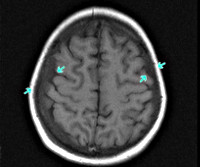

• Томографические исследования. Методы нейровизуализации имеют решающее значение в случаях скрытой нейролейкемии, при выявлении изменений цереброспинальной жидкости без соответствующей клиники заболевания. КТ головного мозга визуализирует очаги инфильтрации как гиподенсивные. Церебральная МРТ подтверждает наличие инфильтратов, позволяет более точно оценить их размер и расположение. Однако нейровизуализация не диагностирует природу инфильтратов, поэтому интерпретируется в комплексе с другими диагностическими данными.